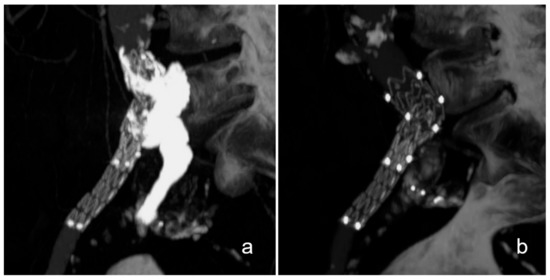

3.2. Case Descriptions